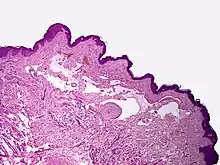

Microscopically, the vesicles in lymphangioma circumscriptum are greatly dilated lymph channels that cause the papillary dermis to expand. They may be associated with acanthosis and hyperkeratosis. There are many channels in the upper dermis which often extend to the subcutis (the deeper layer of the dermis, containing mostly fat and connective tissue). The deeper vessels have large calibers with thick walls which contain smooth muscle. The lumen is filled with lymphatic fluid, but often contains red blood cells, lymphocytes, macrophages, and neutrophils. The channels are lined with flat endothelial cells. The interstitium has many lymphoid cells and shows evidence of fibroplasia (the formation of fibrous tissue). Nodules (A small mass of tissue or aggregation of cells) in cavernous lymphangioma are large, irregular channels in the reticular dermis and subcutaneous tissue that are lined by a single layer of endothelial cells. Also an incomplete layer of smooth muscle also lines the walls of these channels. The stroma consists of loose connective tissue with a lot of inflammatory cells. These tumors usually penetrate muscle. Cystic hygroma is indistinguishable from cavernous lymphangiomas on histology.[7]